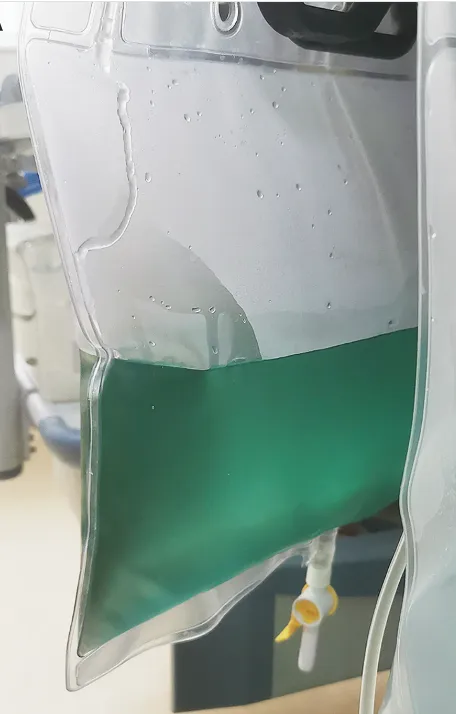

IRA + Icterícia: Um Caso que Exige Investigação Detalhada

IRA + Icterícia: Um Caso que Exige Investigação Detalhada